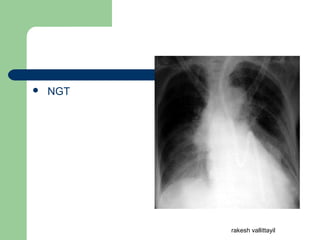

 NGT